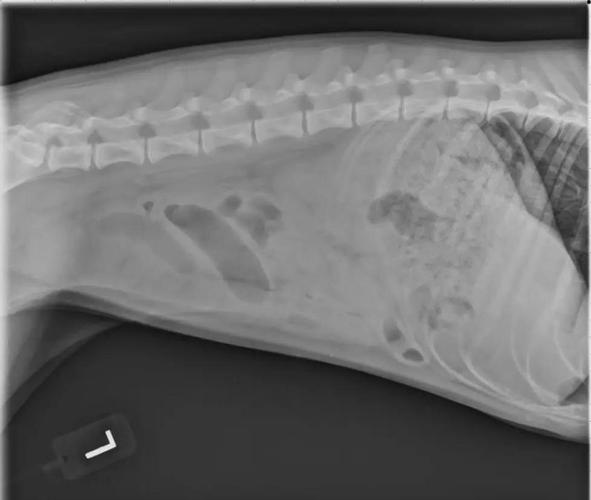

狗狗肠套叠如果不及时治疗,通常会在一周内迅速死亡。肠套叠是指肠道的一段向另一段套入,造成肠道阻塞的一种疾病。这种疾病会影响狗狗的正常消化和排便,进而出现腹部胀痛、呕吐、排便困难等症状。

〖Three〗、狗狗肠套叠如果不及时治疗,通常会在一周内迅速死亡。肠套叠是指肠道的一段向另一段套入,造成肠道阻塞的一种疾病。这种疾病会影响狗狗的正常消化和排便,进而出现腹部胀痛、呕吐、排便困难等症状。

狗狗肠套叠的治疗,需要根据病情的严重情况采取不同的措施。对于病情较轻的肠套叠,可以试用空气灌肠复位,或用温肥皂水灌肠复位。必要时需要使用止痛药和麻醉药,也可使初期肠套叠自然复位。对于病情严重的患犬,必须进行手术整复,如果套叠时间过长,套叠肠管已发生淤血坏死,须切除套叠肠管,作肠管吻合术。